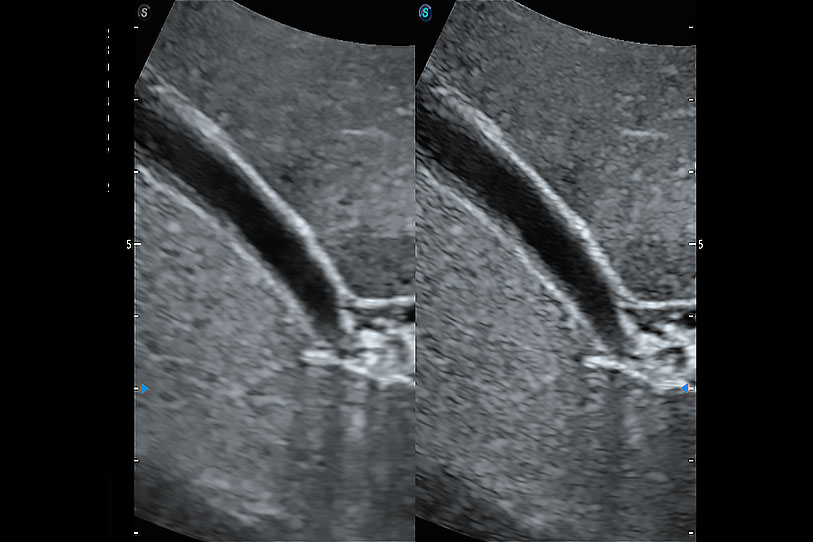

ProPet 70 進(jìn)一步提升了微米成像算法,更加注重對基礎(chǔ)原始圖像的還原和保留,在有效減少斑點(diǎn)噪聲、增強(qiáng)組織邊界顯示的同時(shí),避免過度優(yōu)化丟失真實(shí)的解剖信息。

增強(qiáng)穿刺針在動物解剖結(jié)構(gòu)中的位置,提高穿刺介入的安全性和準(zhǔn)確性。